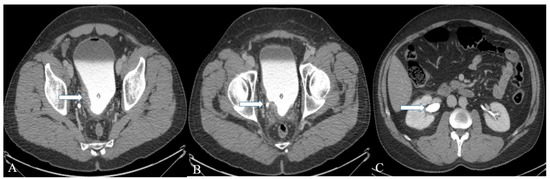

Figure 8. A 40-year-old female with urinary bladder NENs. Axial CT (A) pre-contrast and (B) delayed post-contrast images with coronal reconstruction (C) pre-contrast and (D) post-contrast reveal a 4.8 × 2.5 cm mass (arrows) at the proper aspect of the urinary bladder, showing faint peripheral calcification. Pathology revealed a neuroendocrine tumor of the urinary bladder.

Figure 9. A 32-year-old female with urinary bladder NENs. Axial CT post-contrast (A) shows soft tissue thickening (arrow) mounting to mass formation involving the right lateral and posterior urinary bladder wall. (B,C) It is seen narrowing (arrow in (B)) the right ureterovesical junction with secondary mild right hydroureteronephrosis (arrow in (C)). This mass seems to infiltrate the perivesical fat. A catheter balloon is seen within the bladder lumen. Pathology of the group revealed urothelial carcinoma with neuroendocrine features and focal glandular differentiation, high grade.